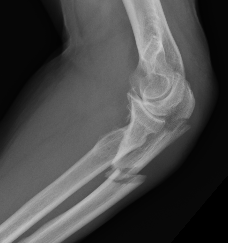

Definition

Elbow dislocation + olecranon fracture + radial head/neck fracture +/- coronoid fracture

Complex proximal ulna fracture with radial head replacement subluxation